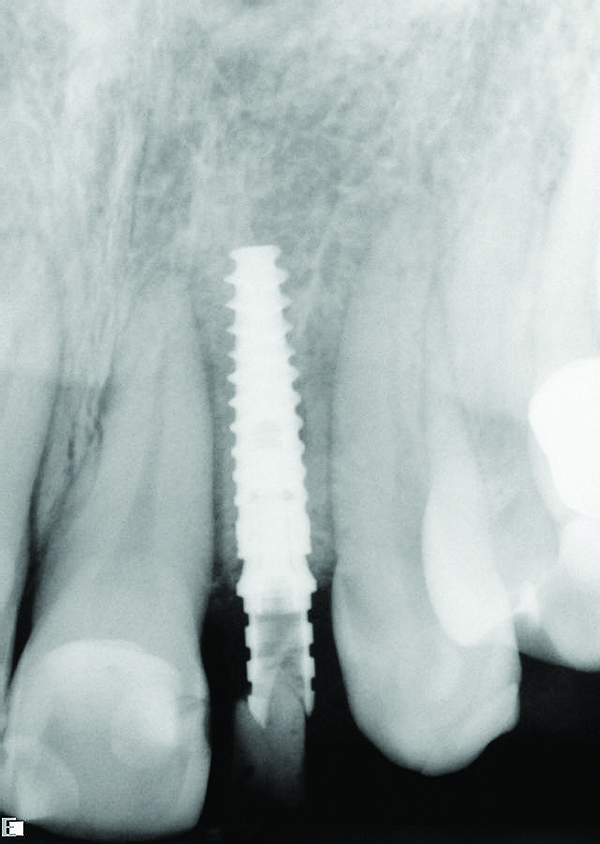

A number of things can be done to improve guide stability and eliminate guide movement during guided surgery. Cassetta et al recommended adequate flap elevation so as not to impinge upon the guide, to thus eliminate flap tension as a cause for guide instability.11 This requires sufficient and often extensive flap reflection. Additionally, they recommended guide fixation using horizontally placed bone fixation pins. The pins should be arranged at least as a tripod for maximum guide stability during surgery. In these cases horizontal osteotomies are planned presurgically during the digital planning, and at the time of surgery they are prepared through the mucosa into the underlying alveolar bone, through which the fixation pins are placed. It is important to pay close attention in planning and later placing horizontal fixation pins so as to avoid vital structures such as adjacent tooth roots and neurovascular canals. In dentate and partially dentate patients, the surgeon can place a thin layer of flowable material such as bite registration material on the inner surface of the guide, then immediately seat the guide in proper position. Figure 7 through Figure 9 demonstrate this technique; the guide is secured in proper position, assuring its stability and accurately creating an osteotomy.

Fig 7. CAD/CAM implant surgical guide to replace congenitally missing tooth No. 10.

Figure 7

Fig 8. Tooth-supported implant surgical guide stabilized in place using bite registration material to avoid movement of the guide

during implant surgery.

Figure 8

Fig 9. Radiograph taken at the time of implant placement confirming that the implant is precisely positioned, matching the presurgical plan.

Figure 9